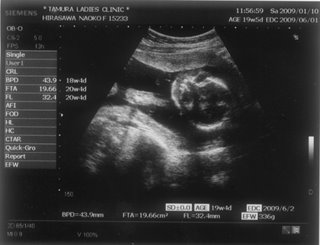

お腹の赤ちゃんは、今日で24週と4日。あっという間に7ヶ月突入です

![]() お腹もドンドン、食欲もドンドン出ていてあしたの4回目の検診コワーイ ![]() 妊娠発覚から三ヶ月半、なのにもう妊娠7ヶ月!頭がついていきません ![]() でも、毎日激しくなる胎動に感激している日々です ![]() 一回目の検診から4週後、2度目の検診に行ってきました。 2008年12月13日 赤ちゃんは15週と5日 ![]() 順調でした ![]() 左側から頭、胴体、足が写っていまーす ![]() 今回は4Dの機械も入り毎回撮影してくれるそうでーす ![]() 赤ちゃんは、ゴツゴツした背中だけを 見せ、顔はみせてくれませんでした~ ![]() それから4週後、3回目の検診。 2009年1月10日 赤ちゃんは19週と5日 ![]() 336gくらいになったようです ![]() 4D ようやく顔をみせてくれました ![]() かなりエイリアン ですが、フニュフニュ可愛かったです![]() 性別が わかりそうだったんですが、ソラ同様肝心なトコロをみせてくれませんでした ![]() もちろんどっちでもいいんですが、しりたーい ![]() 明日わかるかな ![]() ソラも赤ちゃんがテレビに映ったり、雑誌に載っていたり、 出かけ先で見かけたりすると、「ベイビー ![]() 」と大きな声で、何度も何度も興奮気味に言います ![]() 自分もまだまだ赤ちゃんなのに、「ベイビー」は自分より 小さくて可愛いものだと感じ始めているようです ![]() わたしは、一週間に1度だけ1歳になったばかりの 女の子を預かっています。 ソラは、その子が自分のオモチャを使うことに対して 少しイヤな気がしているようです ![]() 少し前までは「ドーゾー」と相手に有無を言わせず 何でも渡していたけど、どんどん自我が出てきているみたいですね~ そんな感じでオモチャを取り合いしながら、シェアすることも学んでいます。 でも女の子が寝ると、さすがに可愛いと思ったらしく、 頭をナデナデ、チュしていました ![]() こんにちわ☆